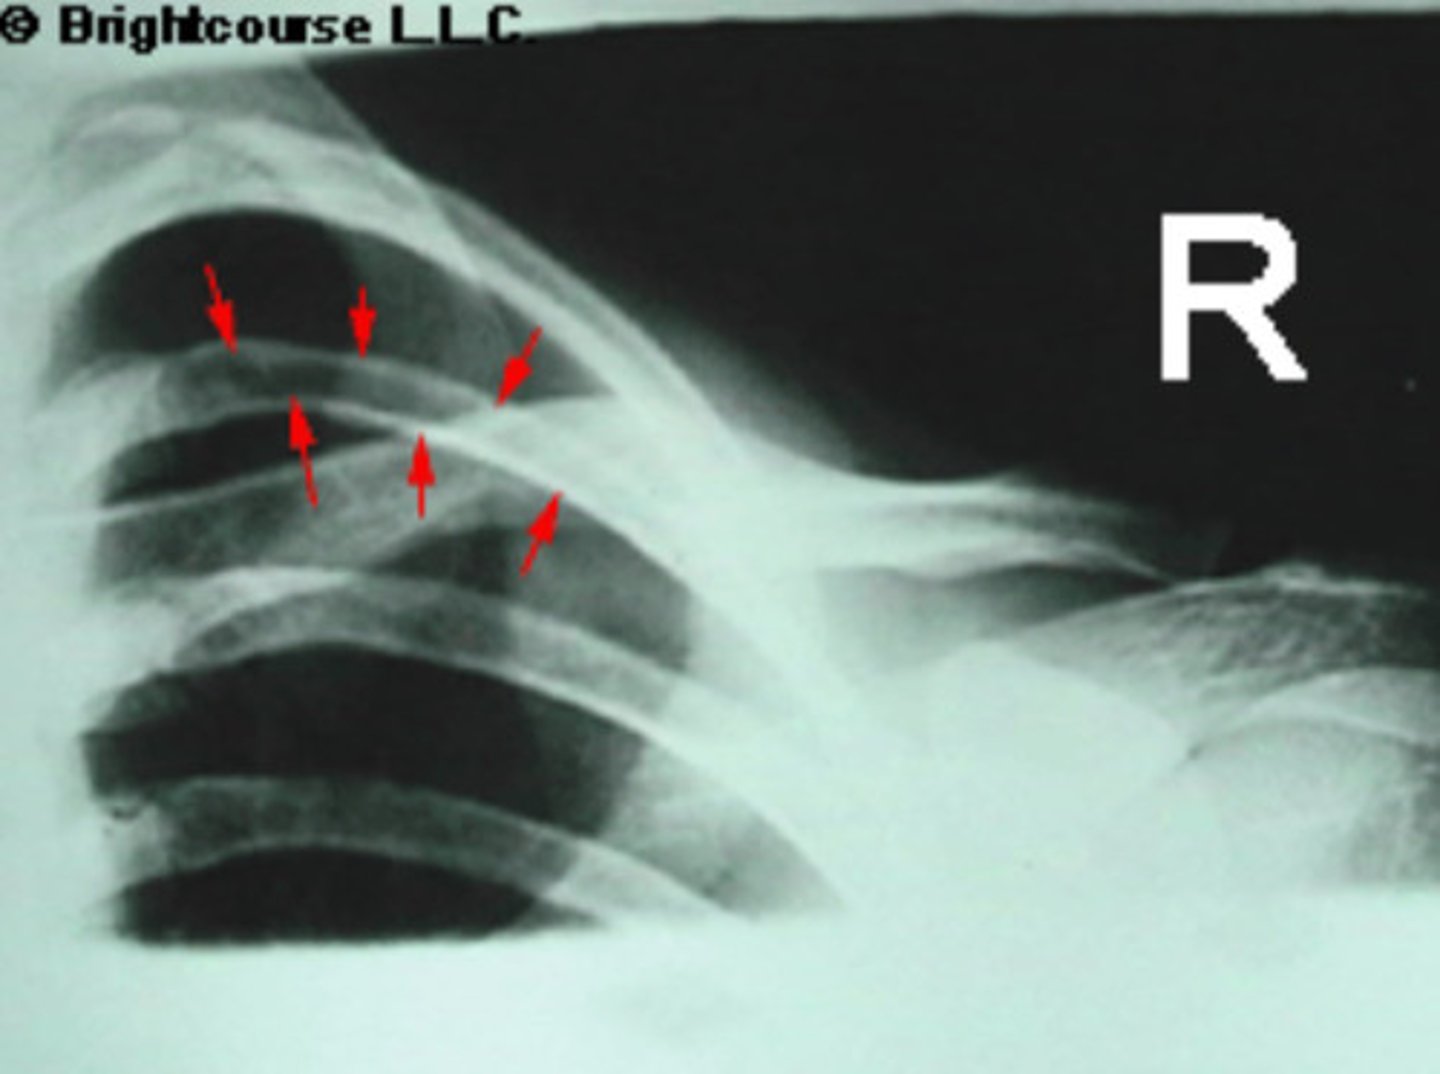

Soft tissue

What is being pointed out by the arrows in this image?

1st rib

What is being pointed out by the arrows in the image?

3rd rib